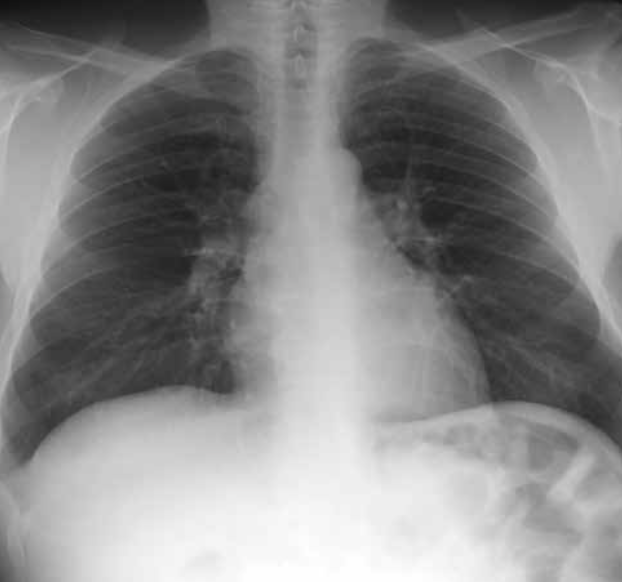

Signo de la silueta en placa de tórax PA.

Neumonía del lóbulo inferior izquierdo. La consolidación del lóbulo inferior izquierdo borra el contorno del hemidiafragma izquierdo (infiltrado retrocardiaco).